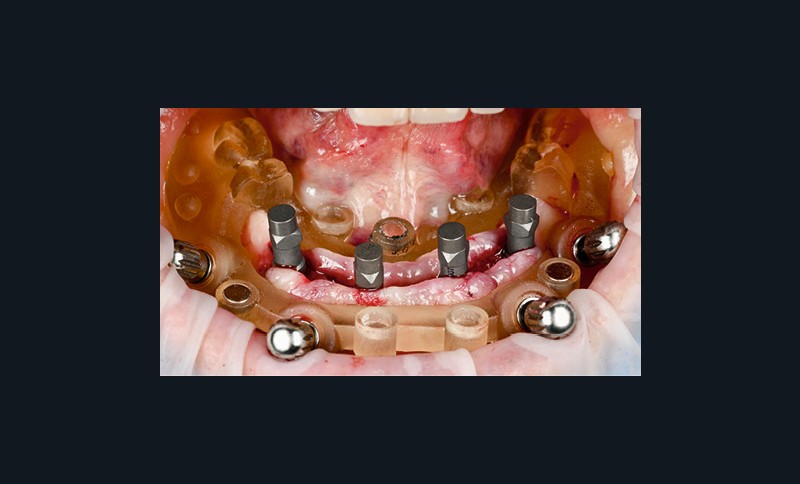

Un premier étage, appelé guide base, est fixé sur le maxillaire à implanter et servira de socle pour les étages supérieurs à empiler (fig. 2). Il doit être aussi rigide que stable pour supporter les contraintes pendant toute la durée de l’intervention : celles du forage implantaire comme celles des poses et déposes des étages supérieurs. Son bon positionnement est donc crucial car il déterminera celui des autres étages. Il peut également servir de repère en fin de procédure, tel un guide de scannage, pour réaliser une empreinte optique (fig. 3). Les appuis sont aussi divers qu’avec un guide statique conventionnel :

- appui dentaire : il est le plus fiable car son positionnement est permis grâce à des points fixes (fig. 4). Il reste bien sûr dépendant de la précision de l’alignement entre le STL de l’empreinte optique et le DICOM de l’examen CBCT ;